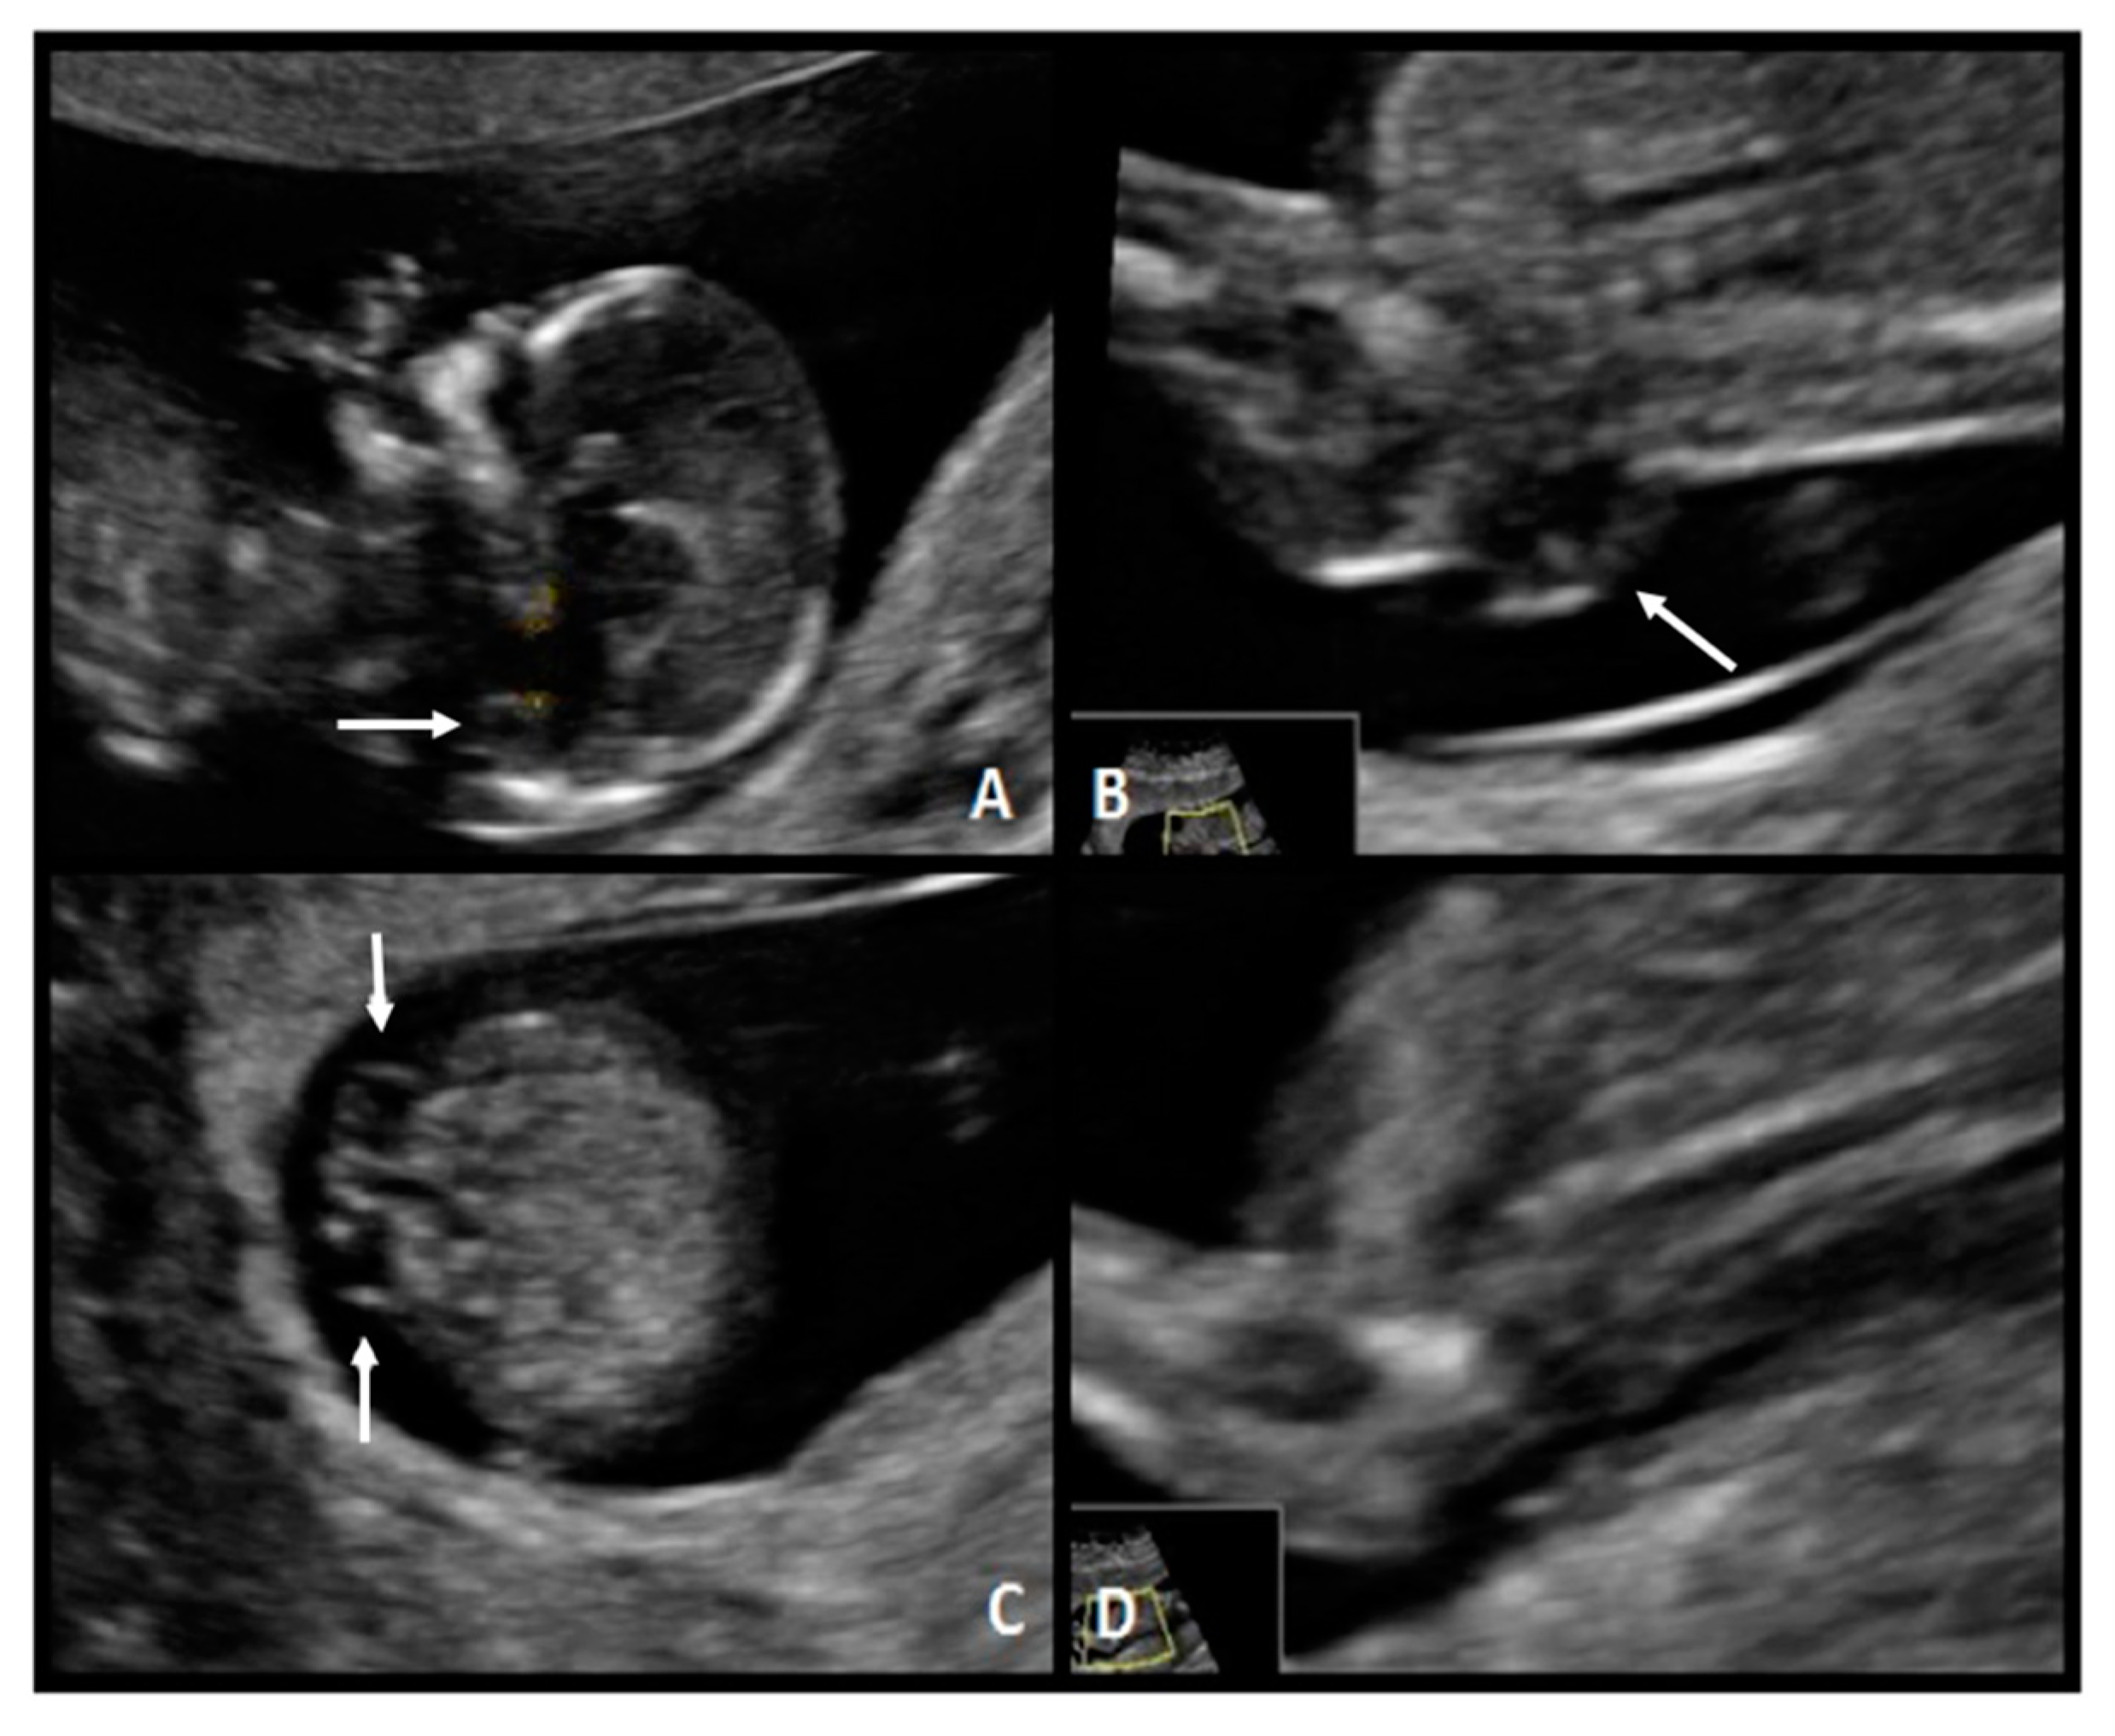

A 37-year-old woman G5 P3 with a previous daughter with Down syndrome was referred at 12.2 weeks of gestation. The fetus had a CRL of 66.5 mm, NT of 1.4 mm, present nasal bone, and absence of the IT. The diagnosis of spina bifida was suspected and confirmed at 21 weeks (Figure 5). A sacral (S1–S4) SBA was observed. After multidisciplinary counseling, the couple decided on postnatal surgical repair.

Figure 5. Case 4. (A) Mid-sagittal plane of the fetal face demonstrates compression of the fourth ventricle with no visible IT (*). (B) Ultrasound view of the lower back with a lumbar spine defect (white arrow). (C) Sagittal plane of the spine shows the neural tube defect (white arrow). (D) No evident IT.